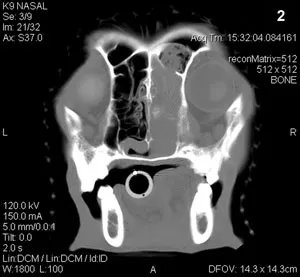

A CBC, serum biochemical profile, and urinalysis showed no abnormalities. Prothrombin time and partial thromboplastin time were normal. Thoracic radiographs were unremarkable. Lymph node aspirates from both submandibular lymph nodes revealed mild reactivity. Computed tomography (Figure 2) was done, followed by rhinoscopy using a rigid scope for obtaining biopsies.

CT (Figure 3) revealed a large, expansile mass within the right nasal cavity, with destruction of the frontal and lacrimal bones (green arrow) and extension into the right orbit (yellow arrow) and frontal sinus (red arrowhead). There was also extension of the mass into the right nasopharynx (green arrowhead). Extensive turbinate destruction was identified.

CT is usually the preferred imaging modality for suspected nasal tumors. Scans obtained both with and without contrast enhancement should be done because different information can be obtained from each study. The noncontrast study should be done first to evaluate the bone and nasal turbinates for destruction. Thin (1 mm) slices should be done through the area of the cribriform plate tolook for bone lysis and invasion into the olfactory bulb of the brain.

The contrast scan can help differentiate soft tissue (tumor) from mucus since tumors are better visualized with enhancement. Further, since the meninges will often contrast enhance, this strategy can be helpful to determine if there is tumor invasion into the brain, which can carry a worse prognosis. All imaging should be completed before rhinoscopy is done or blind biopmasies are taken because bleeding during the procedure can complicate image interpretation.